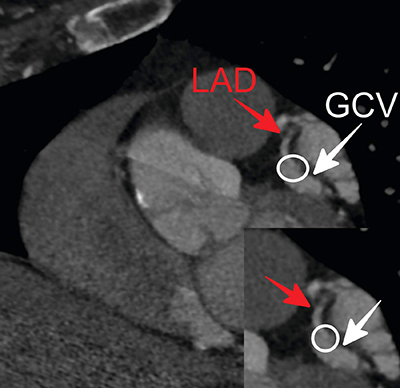

冠状动脉瘘(CAF)是冠状动脉的异常沟通,即静脉回路绕过心肌内的正常毛细血管。冠状动脉-心脏静脉瘘是第三种最常见的 CAF,占病例总数的 7%。心电图门控心脏计算机断层扫描(CT)血管造影术因其较高的时空分辨率和较短的采集时间,已成为无创诊断的替代方法。在此,我们旨在介绍一位 77 岁女性的左前降支冠状动脉在远端开口于心脏大静脉,与冠状动脉-心脏静脉瘘一致。教学要点:冠状动脉 CT 血管造影可详细评估冠状动脉瘘的复杂解剖结构,而无需采用侵入性方法。

Coronary artery fistulas (CAFs) are abnormal communications of coronary arteries whereby venous circuits bypass the normal capillaries within the myocardium. Coronary artery-to-cardiac vein fistula is the third most common type of CAF, accounting for 7% of cases. Electrocardiographic-gated cardiac computed tomographic (CT) angiography has emerged as a noninvasive alternative method of choice for diagnosis due to its high spatial and temporal resolution and short acquisition time. Herein, we aimed to present a left anterior descending coronary artery opened into the greater cardiac vein at the distal level, consistent with a coronary artery-to-cardiac vein fistula in a 77-year-old woman. Teaching point: Coronary artery CT angiography provides a detailed evaluation of the complex anatomy of coronary artery fistula without the need for invasive methods.